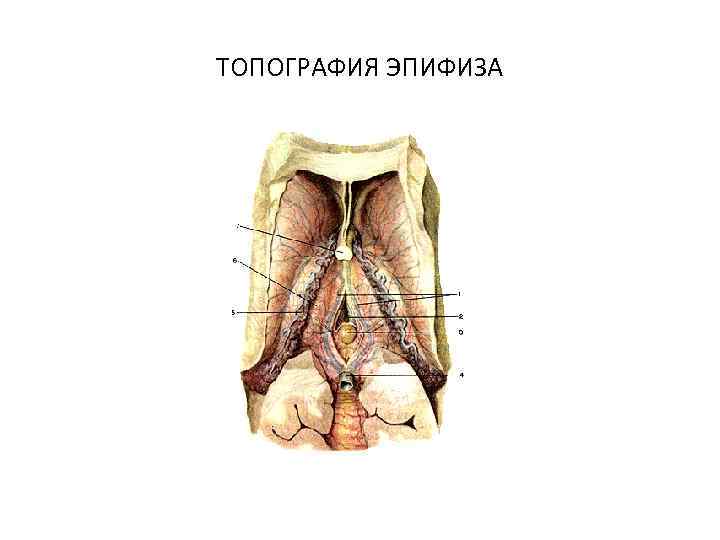

ТОПОГРАФИЯ ЭПИФИЗА

ТОПОГРАФИЯ ЭПИФИЗА